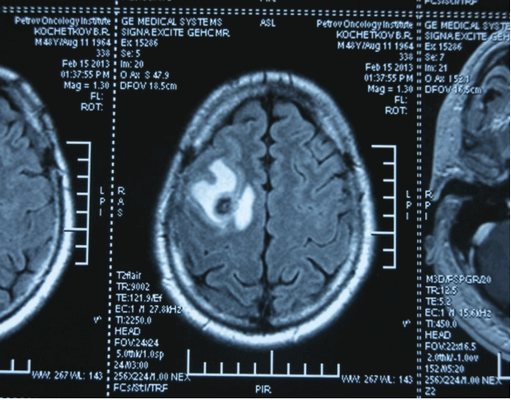

Также выполняют МРТ головного мозга, чтобы выявить наличие метастазов в нем.

![Метастаз в головной мозг при герминогенных опухолях (МРТ головного мозга)]()

Метастаз в головной мозг при герминогенных опухолях (МРТ головного мозга)